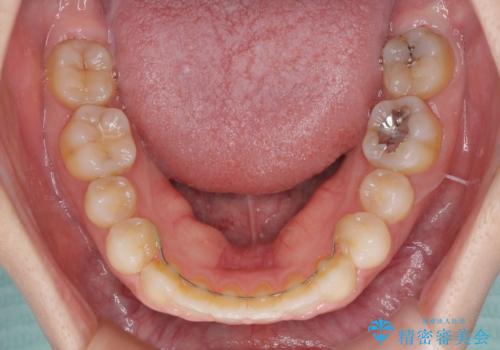

- 歯の欠損による隙間だらけの歯並びを気にして来院された患者様です。

上顎左右1本ずつ欠損していたため、歯列矯正により欠損部位にスペースを集め、その後欠損部位をインプラントにて補綴することとしました。

インビザラインによる矯正治療も提案しましたが、長時間の装着や自己管理が難しいとお考えで、ワイヤーによる矯正治療を行いました。

歯並びは比較的早めに整いましたが、インプラントを埋入するにあたって前後の歯根位置を改善する必要があり、矯正治療に期間を要することとなりました。